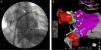

Fluoroscopy with PentaRay® catheter positioned in the left superior pulmonary vein (A); image from the CARTO® system showing the PentaRay® catheter in the left inferior pulmonary vein (B). VPIE: left inferior pulmonary vein; VPSE: left superior pulmonary vein; yellow arrow: PentaRay® catheter; white arrow: ablation catheter; black arrow: decapolar catheter in the coronary sinus.

Voltage map in sinus rhythm, visualized from the left atrial posterior wall using the CARTO® system. VPID: right inferior pulmonary vein; VPIE: left inferior pulmonary vein; VPSD: right superior pulmonary vein; VPSE: left superior pulmonary vein; purple area: normal voltage; red area: low voltage.